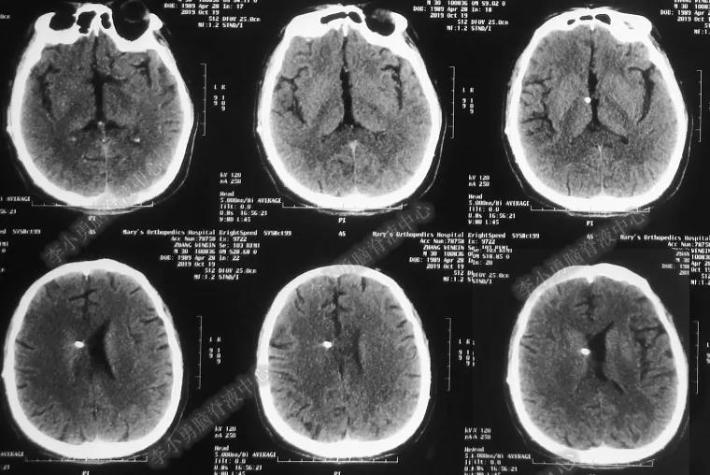

但医生认为头晕等症状均与脑积水有关,因此于2019年4月19日行脑室腹腔分流术。术后次日即2019年4月20日,头晕及视力下降症状就有好转,复查头颅CT见引流管位置好,脑室有所缩小(图-5),术后10天“治愈”出院。

图-5:2019年4月20日头CT